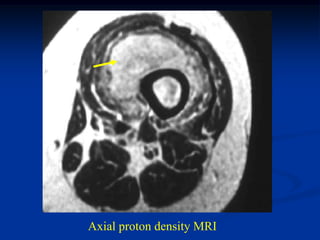

Case #261

62 year female

MFH anterior thigh

AP x-ray

Sagittal proton

density MRI

Sagittal T-2 MRI

Axial proton density MRI

Axial T-2 MRI